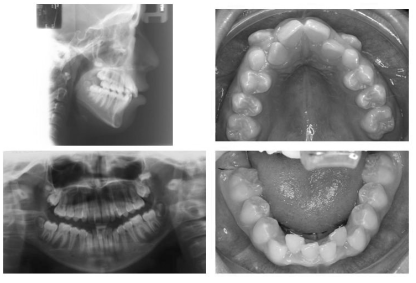

La advertencia más importante de que Damon ofrece a los clínicos es no es usar su mecánica corriente con su sistema, y no podía estar más de acuerdo. Cuando empecé a usar el sistema de Damon primero, continué usando la secuencia regular de de arco alambres y vi poca ventaja a estos nuevos brackets más costosos. Sin embargo, cuando empecé a usar los brackets de acuerdo con el consejo de Dr. Damon, empecé a ver cambios extraordinarios. El siguiente paciente ilustra las típicas respuestas para la biomecánica brindada por el sistema de Damon:

Pre-treatment

The maxiliary posterior transverse arch adaptation resulted in an 8 mm change at the firt premolars

The maxiliary posterior transverse arch adaptation resulted in an 7 mm change at the firt molars

The mandibular posterior transverse arch adaptation resulted in an 6 mm change at the firt premolars

The mandibular posterior transverse arch adaptation resulted in an 6 mm change at the firt molars